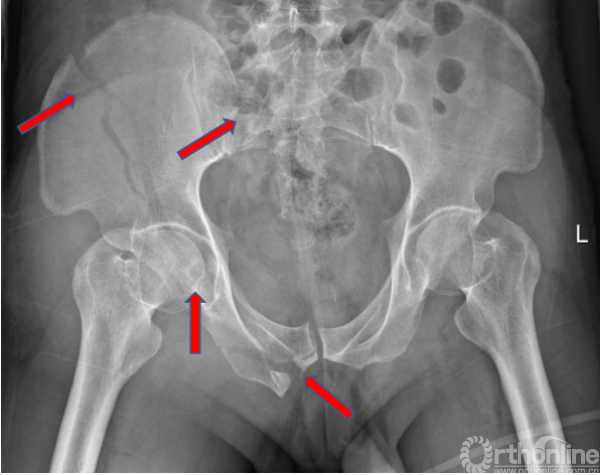

术前X线(2017.09.17)

骨盆正位、骨盆入口位、骨盆出口位